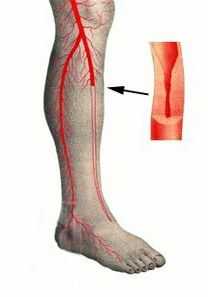

Подобное поражение сосудов можно вынести в отдельный раздел, так как по медицинской статистике примерно в половине всех известных случаев фиксируется именно окклюзия бедренной артерии и подколенной артерии.

Симптомы подобной окклюзии детально изучены и описаны, а в англоязычной медицинской литературе даже выведено правило «пяти Р» - характерных проявлений, при возникновении хотя бы одного из них требуется экстренное проведение диагностики и назначение лечения:

- Pain - боль - разлитая, обширная область ниже участка поражения, усиливающаяся и не облегчающаяся при изменении положения ноги.

- Pulselessness - исчезновение пульса в характерных местах близкого расположения артерий. Подобный симптом врачами используется для более точного определения места окклюзии.

- Pallor - бледность, цвет кожи ниже пораженного участка вначале бледнеет, потом проявляются пятна цианоза. Температура таких участков стремительно снижается.

- Paresthesia - парезтезия, чувство онемения, покалывания, «мурашек» - верные признаки сосудистого поражения. Пропадает чувствительность к прикосновениям, может настать полное онемение с исчезновением болезненных ощущений.

- Paralysis - паралич конечности, нарушение ее двигательной функции - проявление обширной ишемии участка.

Несвоевременное принятие мер (свыше 4 - 6 часов) может привести к необратимым некротическим изменениям в тканях, развитию гангренозного процесса. Окклюзия артерий конечностей - одна из основных причин инвалидности и ампутации ног, особенно у мужчин в возрасте старше 60 лет.